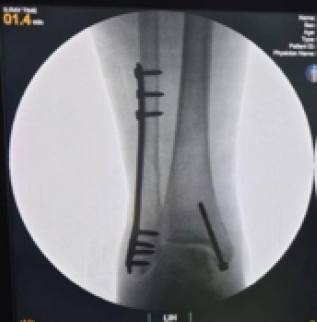

Comparative Study of Minimally Invasive Plate Osteosynthesis Versus Open Reduction and Internal Fixation in the Treatment of Distal Fibular Fractures

Arumoy Bhuimali , Aniruddha Mondal , Satyaki Dandi , Aniket Koley

………………………………p.369-378